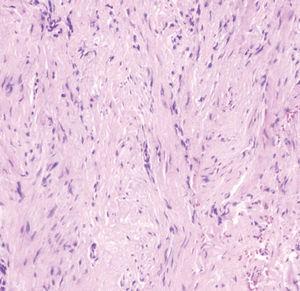

En la primera visita se realizó una analítica general, que no mostró hallazgos patológicos, y una serología viral, incluyendo virus exantemáticos, que resultó negativa. La radiografía de la mano sólo mostraba un engrosamiento focal de partes blandas, sin afectación ósea subyacente. Se revisaron las biopsias correspondientes a la lesiones extirpadas inicialmente (figs. 3-5).

Fig. 5.--A mayor aumento se observaba la presencia en el citoplasma de las células de inclusiones eosinofílicas yuxtanucleares. (Hematoxilina-eosina, x400.)

El examen histopatológico correspondiente a la extirpación previamente realizada mostraba una proliferación mal delimitada localizada en la dermis y el tejido celular subcutáneo, que se extendía hasta la unión dermoepidérmica, compuesta por fascículos entrelazados de células fusiformes (figs. 3 y 4). No se observaban células ni mitosis atípicas. A mayor aumento, en el citoplasma de algunas de estas células se apreciaba la presencia de inclusiones intracitoplasmáticas eosinofílicas, algunas de localización perinuclear (fig. 5). No se realizó estudio inmunohistoquímico.

La histología es característica. La biopsia cutánea muestra una proliferación mal delimitada en dermis y tejido celular subcutáneo, compuesta por células fusiformes, que corresponden a fibroblastos y miofibroblastos. Estas células se disponen formando fascículos entrelazados, rodeados por una estroma de colágeno, que se extienden hasta la unión dermoepidérmica. Las células presentan un núcleo alargado. La epidermis suprayacente no se ve apenas alterada, pero puede presentar ligera hiperqueratosis o acantosis. No se observan atipia nuclear ni mitosis atípicas. A mayor aumento se observan inclusiones eosinofílicas intracitoplasmáticas en las células fusiformes, de localización yuxtanuclear. Estas inclusiones se tiñen de rojo con el tricrómico de Masson y de púrpura con la hematoxilina ácida fosfotúngstica 1-10. El examen mediante microscopia electrónica revela que los cuerpos de inclusión citoplasmáticos se componen de una mezcla de material electrón-denso granular y fibrilar, que corresponde a filamentos similares a la actina 9,12. Se han descrito en adultos casos de un tumor histológicamente similar, pero de localización extradigital 4. Los estudios de inmunohistoquímica muestran en su mayoría positividad a la actina en el citoplasma de las células fusiformes.